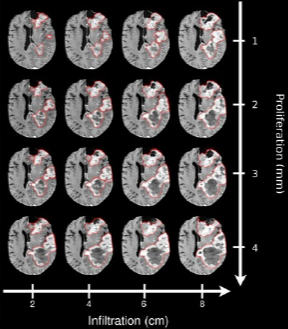

Рис. 1. Пример моделирования состояния пациента. Каждая строка на рисунке соответствует определенному значению, представляющему разные уровни пролиферативной активности. В свою очередь, каждый столбец соответствует определенному значению, указывающему на различную степень инфильтрации тканей. Источник изображения: Medical Physics.